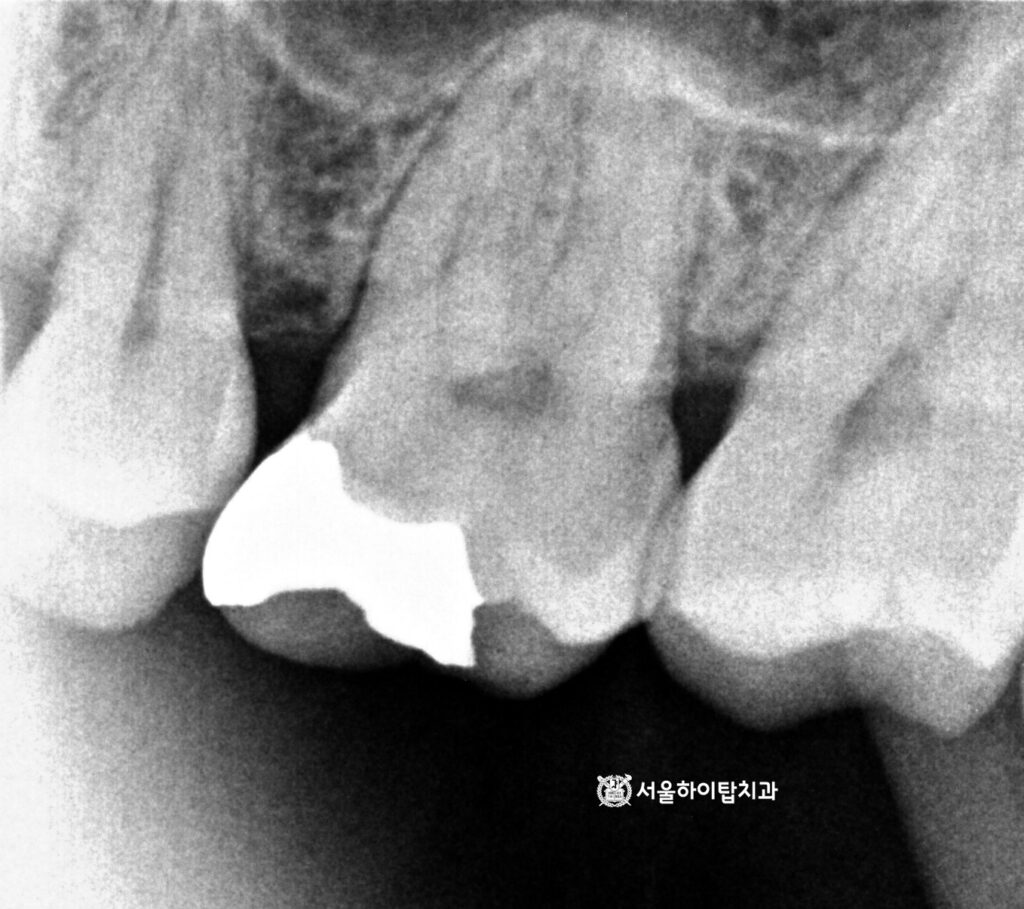

먼저 사진 기준 오른쪽

어금니부터 살펴보겠습니다.

사실 pulpitis은 엑스레이나 PA만으로는

명확히 보이지 않는 경우가 대부분입니다.

동암 치과 에서 그 이유 설명드리자면,

염증이 신경 내부에서 진행되더라도

방사선 사진에는 뚜렷한 변화가

늦게 나타나기 때문입니다.

따라서 뿌리 끝까지 염증이 퍼졌는지,

또는 파절이 동반되었는지를 확인하기 위해|

PA와 환자의 주관적인 증상 평가가 중요합니다.

동암 치과 에서는 다행히 PA로

파절이나 치근단 염증은 보이질 않지만,

이미 저작 시 통증이 느껴지는 상태였기에

치수염이 진행 중임을 알 수 있습니다.